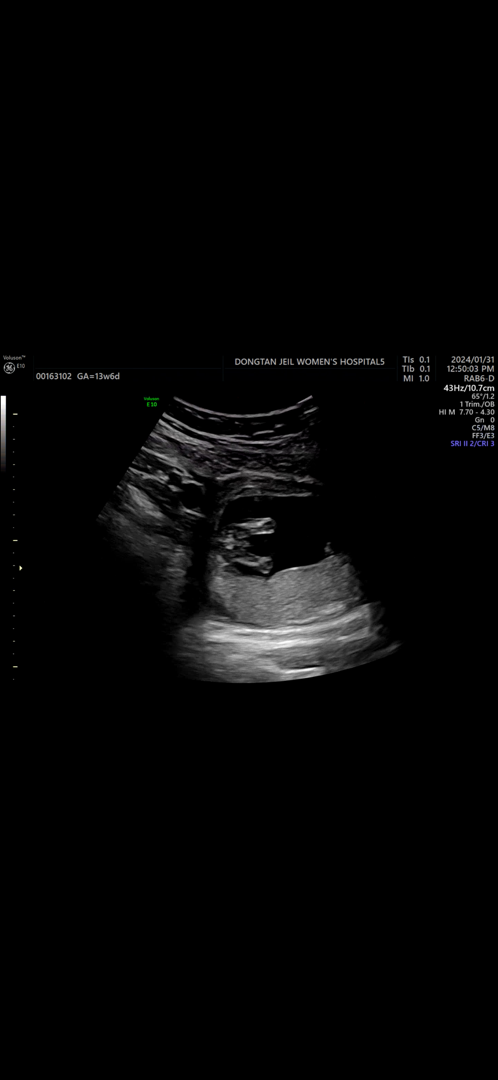

12์ฅฌ๋ ์๋ค ๋ธ ๋ค ๋๊ฐ์ด ๋์์์ด์ ์ 14์ฃผ๊ฐ์ ํ์ธํ์ด์!ใ ใ

1์ฐจ ๊ธฐํ์ ๊ฒ์ฌ๋ ๋ณด์๋ ์ด์ํ์ด๊ธดํ๋ฐ.. ์ ๋ ๊ฒ ๋์ฌ์๊ฐ ์๋ค๊ณ .. ๋ผ๋ผ๋ ์ฌ๋๋ ์๊ณ ๊ทธ๋์์ฉ ํน์ ์๋ค์ผ๊น์?

์๋ค๊ฐ์์

16์ฃผ์ฐจ๋ ๋ค์ ์๋ ค๋๋ฆด๊ฒ์ฉ!!